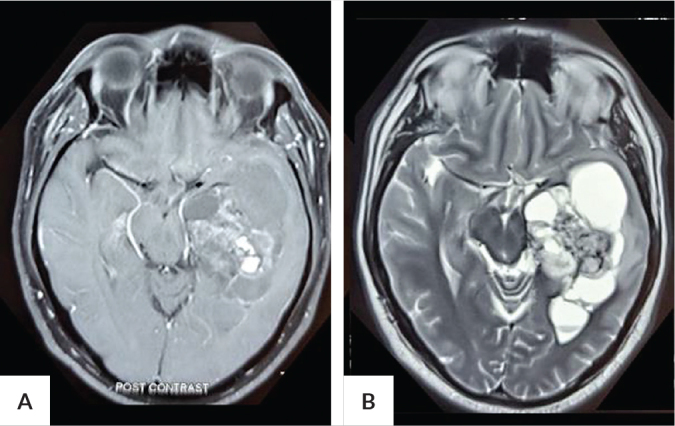

我们报告一个39岁的男性谁有全身性强直阵挛发作与意识丧失。经检查诊断为左颞叶肿瘤。他接受了肿块切除术,随之而来的是颞叶脑组织的丢失,并在术后立即发现有完全的右侧同义性偏视。光学相干断层扫描(OCT)显示右眼的鼻间区和左眼的颞下区有相同的变薄。本病例通过中断下视光辐射表现出跨突触逆行变性,及其对受影响视网膜视野的结构和功能的相应影响。颞叶病变不仅可引起病变侧对侧相同的视野缺损,而且可导致病变侧同侧的双眼黄斑神经节细胞复合体相同的部门性变薄。

We report a 39-year-old male who had generalized tonic-clonic seizure with loss of awareness. Investigations led to a diagnosis of a left temporal lobe tumor. He underwent resection of the mass with consequent loss of brain tissue in the temporal lobe and was found to have a complete right homonymous hemianopia in the immediate postoperative period. Macular ganglion cell analysis on optical coherence tomography (OCT) showed homonymous thinning affecting the inferonasal sector in the right eye and inferotemporal sector in the left eye. This case demonstrates transsynaptic retrograde degeneration through the interruption of the inferior optic radiation, and its corresponding effect on the structure and function of the affected retinal field. Temporal lobe lesions may cause not only a homonymous visual field defect contralateral to the side of the lesion but also result to homonymous sectoral thinning of the macular ganglion cell complexes in both eyes located ipsilateral to the side of the lesion.